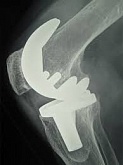

Endoprothetik des Kniegelenks

In den späten Stadien der Arthrose des Knies durch eine ausgeprägte Begrenzung der Bewegung begleitet, konstant starke Schmerzen, körperliche Unversehrtheit Verformung bis zur Genesung der einzige Weg ist der Ersatz des betroffenen Gelenks für eine künstliche - Endoprothetik.

Diese Methode ermöglicht es Ihnen, die richtige Form des Gliedes, eine vollständige Palette von Bewegung im Gelenke, zu entlasten ständige Schmerzen und Knirschen bei Bewegung und als Ergebnis wieder herzustellen, signifikant dem Patienten Lebensqualität zu verbessern.

Im Folgenden sind Röntgenaufnahmen und Fotografien, die die Strecke der Bewegung in der betroffenen Gelenke vor und nach der Operation veranschaulichen.